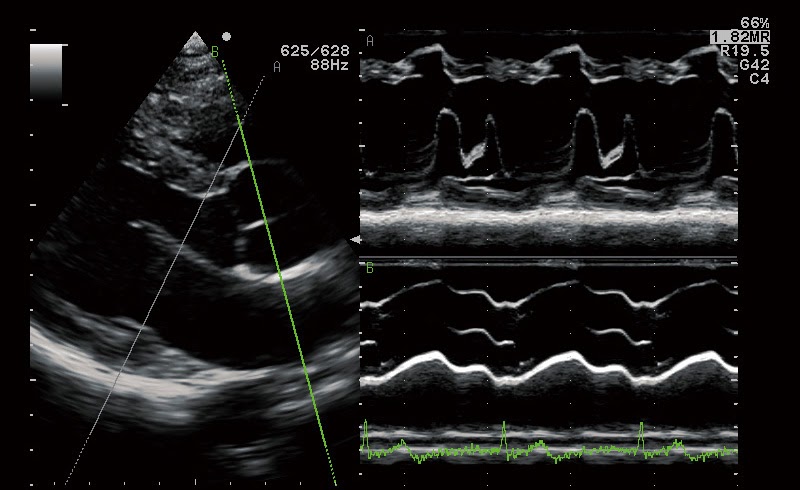

Анатомический М-режим

- Постоянно-волновой допплер

Тканевый допплер